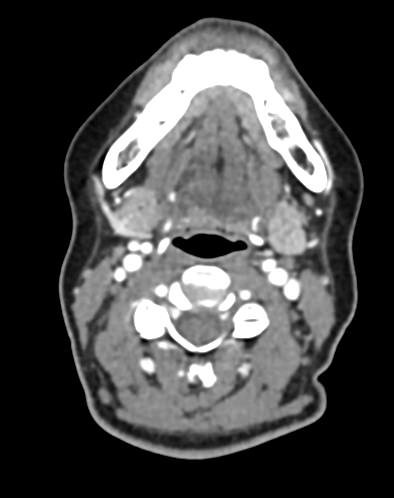

Оптимальным методом обследования гортани и голосовых связок является мультиспиральная компьютерная томография. Метод позволяет подробно визуализировать состояние данной анатомической области и выявить патологические изменения, которые незаметны при ларингоскопии (визуальный осмотр гортани с помощью специальных инструментов), проведении УЗИ и обычной рентгенографии.

Компьютерная томография позволяет оценить состояние костного скелета гортани и особенно важна в оценке состояния хрящей гортани, которые лучше всего визуализируются с помощью данного исследования. В частности, мультиспиральная КТ позволяет выявить распространение рака гортани в ткань щитовидного хряща и другие окружающие структуры.

При подозрении на опухоль гортани нативная мультиспиральная КТ дополняется проведением внутривенного болюсного контрастирования. Для этого пациенту внутривенно вводится контрастный препарат на основе йода.

Контраст хорошо накапливается в патологически измененных участках, за счет этого становятся отчетливо видны на снимках их границы, размеры, точная локализация относительно окружающих здоровых тканей. По характеру накопления контраста можно отличить доброкачественные опухоли от злокачественных, определить степень распространенности процесса, выявить поражение регионарных лимфатических узлов.

На полученных снимках можно оценить состояние всех структурных элементов гортани, голосовых складок, хрящей, а также лимфатических узлов, сосудов и шейных позвонков на исследуемом уровне. Инновационные возможности аппаратов позволяют построить 3D-модель зоны исследования, которая дает наглядную картину пространственного расположения органов, что бывает особенно важно при планировании хирургических операций.